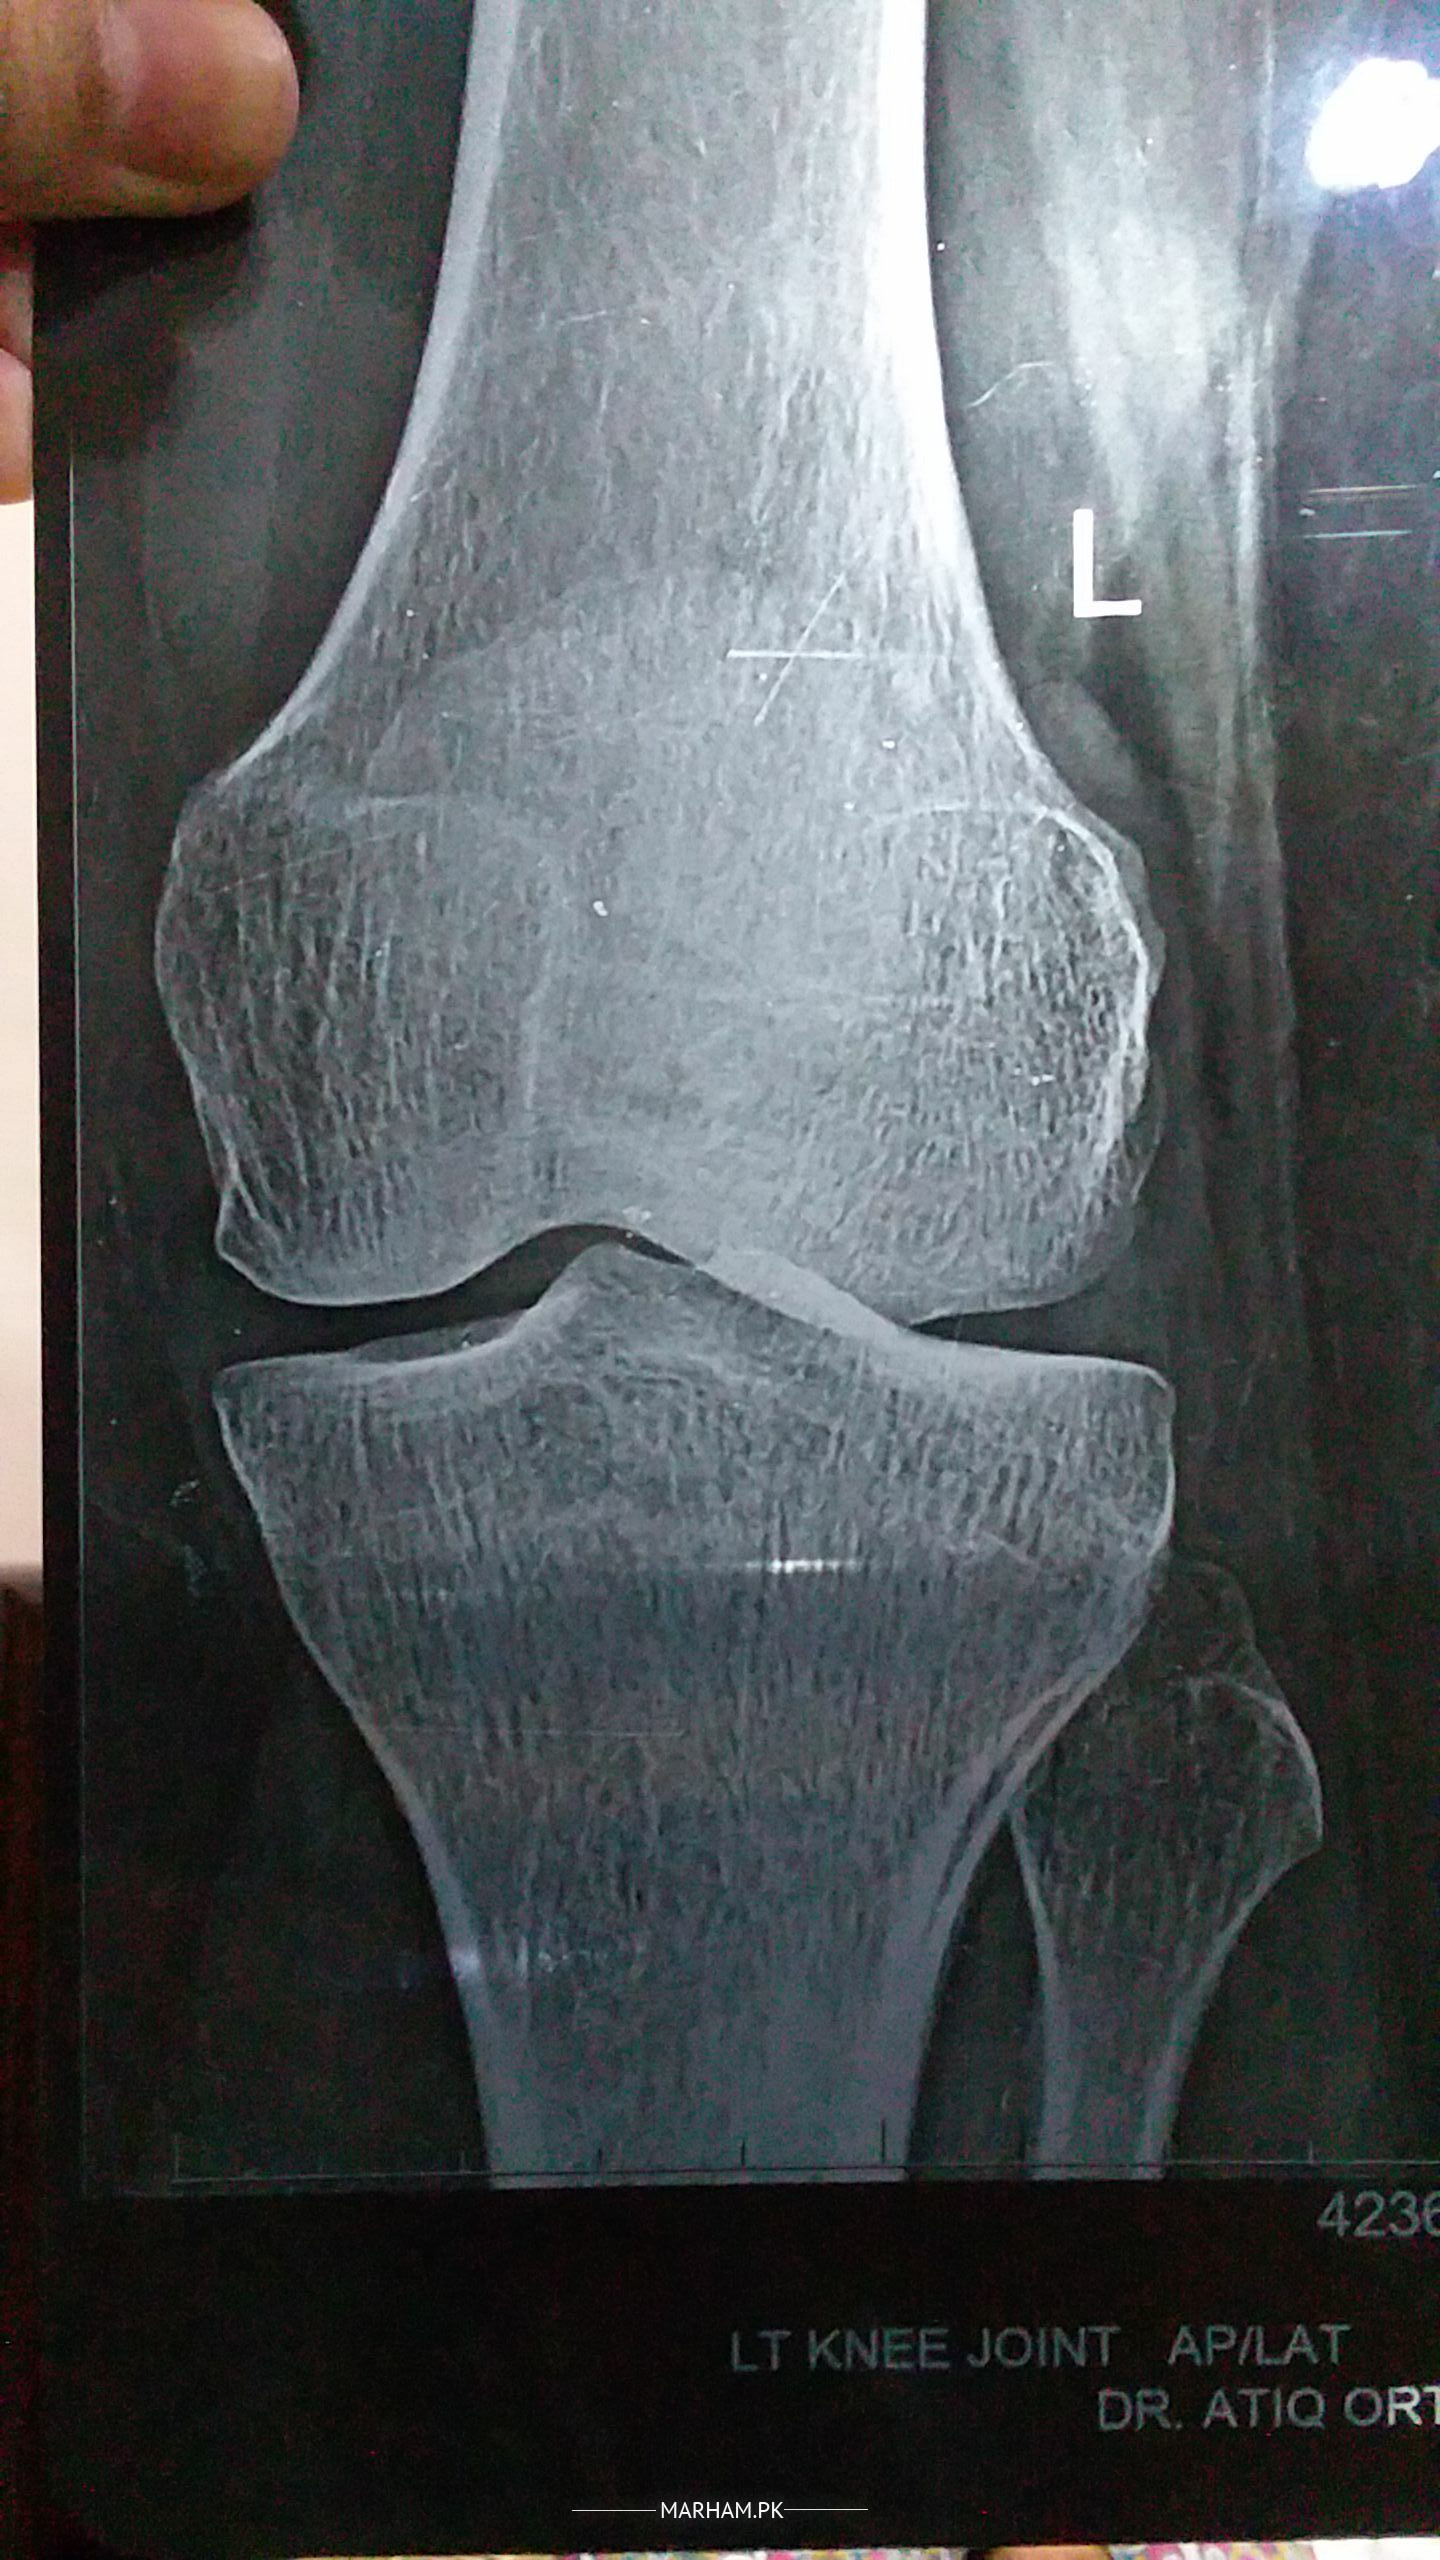

i am having pain in my left knee from almost one year . i am mother of 3 and having difficulty in my routine household work. its painful if i stand for long time or if i sit down while offering prayer. uric acid ,blood sugar, cbc all tests show normal result. this is my recent x-ray report. please guide

was this x ray done in standing position.

if you are overweight, you need to reduce some wright because sometimes more weight on knees causes this pain.

other than this, its difficult to comment on xrays without seeing patients or as other questions.

no i was on x ray bed , my weight is 60kg and height is 5.2